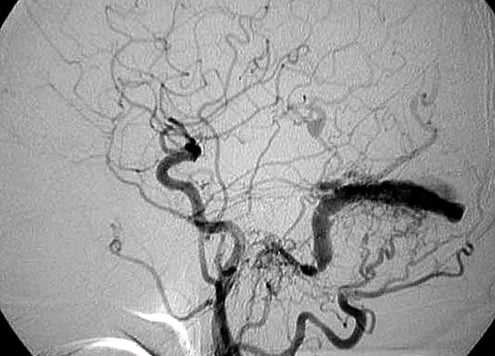

- ДСА показана для подтверждения диагноза, визуализации ангиоархитектоники и планирования лечения

- Расширение питающих артерий

- Преждевременное заполнение и, как правило, расширение вен

- Клубок сосудов расположен между питающими сосудами и дренирующими венами

- Могут встречаться артериальные или венозные аневризмы и стенозы дренирующих вен

- В ряде случаев показано высокоселективное зондирование отдельных питающих артерий

Пиальная артериовенозная мальформация головного мозга . МРТ, Т2-ВИ в аксиальной плоскости (а, b). ДСА в боковой проекции после введения КС в правую внутреннюю сонную артерию (с). Тубулярное отсутствие сигнала от потока в очаге АВМ (черные стрелки) на Т2-ВИ (а). Гипоинтенсивная гематома на Т2-ВИ (дезоксигемоглобин; а, белые стрелки).

Тубулярное отсутствие сигнала на поверхности головного мозга (вена; b, стрелка).

Определяется раннее контрастное усиление поверхностной мозговой вены, начинающейся от ветвей средней мозговой артерии (с, стрелка), и виден располагающийся между ними клубок сосудов (очаг, с)